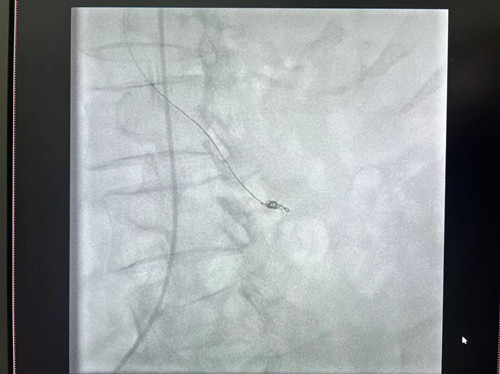

术中,梁琪副教授通过丰富的临床经验判断,与骆雷医生、唐弘喆技师配合,运用Seldinger技术,经右股动脉-肠系膜上动脉成功建立轨道,行肠系膜上动脉造影见空回肠动脉两支小分支远端造影剂呈点片状外漏至肠腔,再沿轨道顺利送入微导管及弹簧圈、可控弹簧圈成功实施栓塞。期间,为了让患者保持清醒,黎姿护士不间断呼喊患者名字,并有条不紊地配合医生工作,及时大声播报生命体征。栓塞后再次造影显示,出血动脉分支远端对比剂外溢未见显示,呈栓塞术后改变,未见异位栓塞征象,达到预期治疗效果。